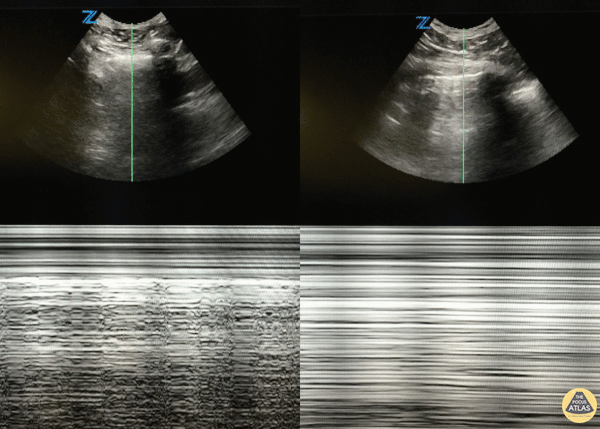

🌪️ Pneumothorax

L’air sépare la plèvre viscérale de la pariétale.

- Absence de glissement pleural : ligne pleurale statique.

- Absence de lignes B, lignes A prédominantes.

- Mode M : « signe du code barre » (lignes horizontales parallèles au-dessus et au-dessous de la plèvre, sans granulation).

- Point poumon : zone de transition entre glissement présent et absent → signe spécifique de pneumothorax.